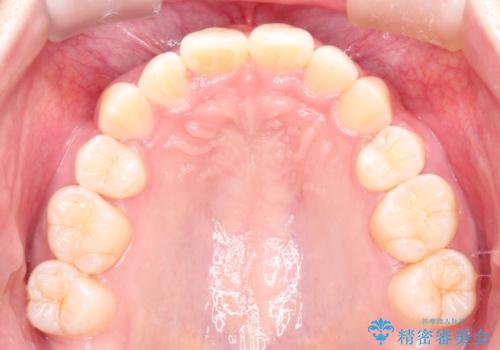

- 前歯のガタガタを主訴に来院されました。

抜歯を行い、インビザラインにて治療を完了しております。